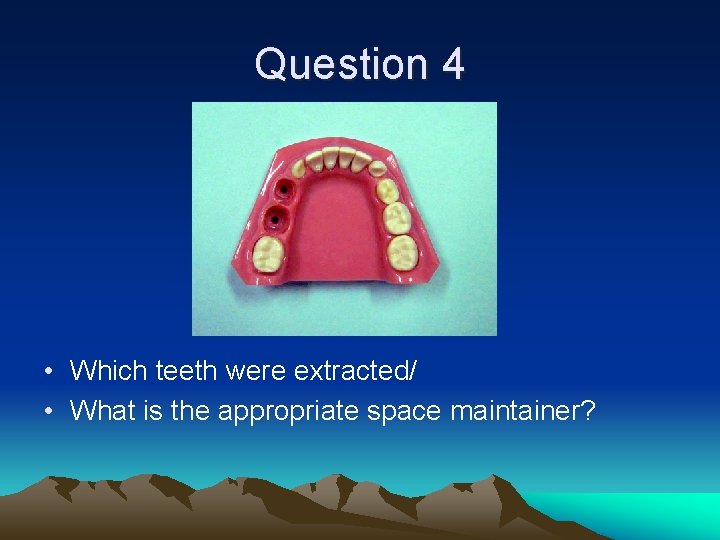

Question 4 • Which teeth were extracted/ • What is the appropriate space maintainer?

Question 4 • Teeth #K and L extracted

Question 4 • Lower Lingual Holding Arch (LLHA) #19 -#30